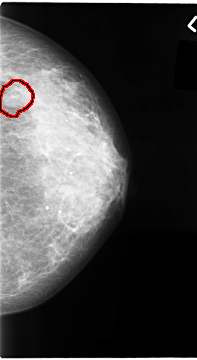

FILE: C_0065_1.LEFT_CC.OVERLAY

TOTAL_ABNORMALITIES 1

ABNORMALITY 1

LESION_TYPE MASS SHAPE OVAL MARGINS MICROLOBULATED

ASSESSMENT 4

SUBTLETY 4

PATHOLOGY MALIGNANT

TOTAL_OUTLINES 1

BOUNDARY